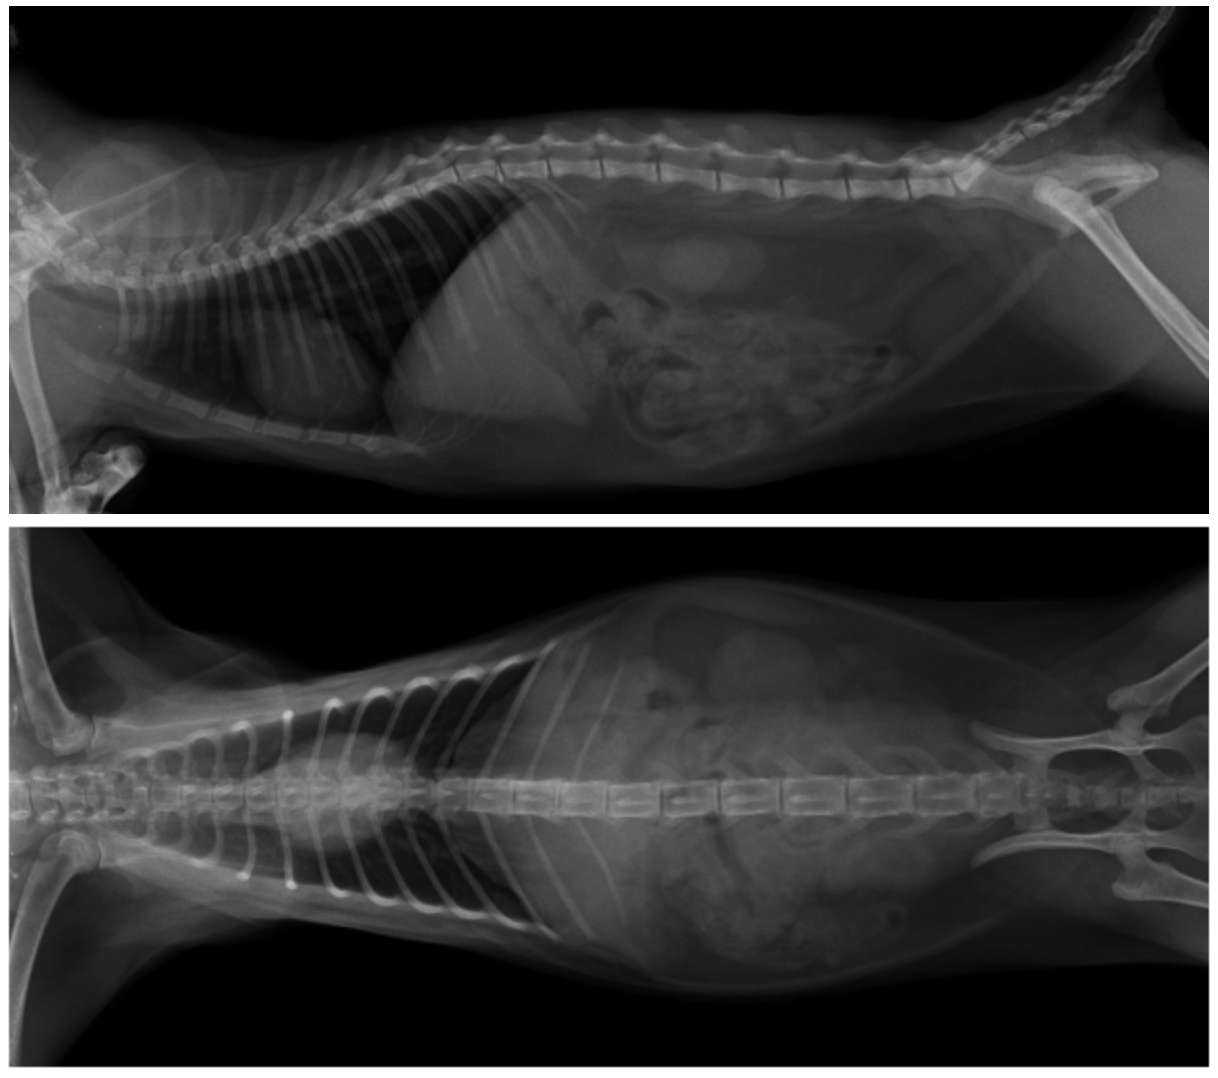

Figure 1 Preoperative CR image

The hemilaminectomy site was redefined preoperatively based on plain X-rays (Figures 1 and 2). Surgical approach: A single incision of the skin and subcutaneous fat was made parallel to the dorsal midline, offset 1 cm (Figure 3). The lumbar multifidus muscle attached to each spinous process was exposed using a scalpel. The lumbar multifidus muscle was then bluntly dissected from the lamina using a periosteal elevator until it reached the facet articular processes (Figure 4). One or two articular processes were dissected in sequence, anterior and posterior to the affected area, and the surrounding tissue was completely separated from the bone to fully expose the articular processes. A rongeur was used to create a bite mark in the lamina anterior and posterior to the affected area, with repeated manipulations to deepen the mark. When cancellous bone was visible (Figure 6) and the dura mater was visualized, the rongeur was discontinued and replaced with a nucleus pulposus forceps, carefully removing the bone from the lamina to expose the medullary cavity. The rongeur and nucleus pulposus forceps were then used alternately to remove the affected articular processes, further exposing the medullary cavity (Figures 7 and 8). After the main surgery, the wound is irrigated, blood clots and bone fragments are removed, a fat pad is placed on the exposed medullary cavity, the lumbar muscles are repositioned, and the dorsal fascia is sutured. The skin tissue is closed routinely.